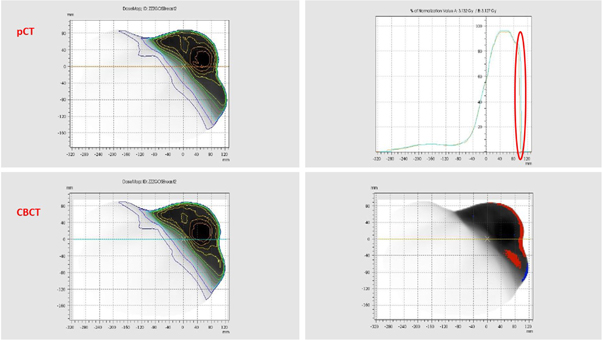

Although 125 kV was previously considered suitable to scan breast patient for dose calculations as per section 3.1.2, their average gamma score was significantly lower than that of pelvis patients. This is because the target area of breast patients was almost always right on the body surface, which was prone to body shape changes and setup inaccuracy. As an example, figure 8 shows the detailed results of Patient No. 2, which has a gamma score of 88.0%. For this patient, the majority of the failed gamma points are a result of body contour changes on the patient surface. When this patient is excluded, the average gamma score of breast patients rose to 95.9%, similar to that of pelvis patients. In addition, the target area of breast patients was more prone to breathing motion compared to pelvis patients. Therefore, it is expected that the average gamma score of breast patients was lower than that of pelvis patients.

Figure 8. Detailed gamma results of Patient ID 2. The top right corner shows dose profile changes, which clearly indicates that there is a gap between the CBCT dose file and the diagnostic planning CT dose file due to body shape variation. The bottom right corner shows the gamma results in 2D, with red indicating points failing gamma analysis that are hotter and blue indicating points failing gamma analysis that are colder. Again, most failed points are near the surface region due to body contour change.

Download figure:

Standard image High-resolution imageSimilarly, the average gamma score for thorax patients was lower than that of pelvis patients despite using the same tube voltage of 125 kV. This is likely because when treating the three patients included in this study, other than the use of 4DCT for delineation and the incorporation of appropriate margins, no other motion management techniques, such as abdominal compression or gating, were adopted. Therefore, the targets in these patients had a similar degree of breathing motion with breast patients, which could compromise the gamma agreement between diagnostic planning CT and CBCT calculations.

In addition, it should be noted that the author's department did not utilize the density override technique proposed by Wiant et al for VMAT lung cases [25], and therefore the doses calculated on the free breathing or the average CT scans might not be able to accurately predict dose of parts of the target volume not occupied by tumour on the diagnostic planning CT scan. However, quantifying the amount of error introduced by different uncertainty components is beyond the scope of this study and therefore is not further discussed here. Although the average gamma score of thorax patients was slightly below 95.0%, based on the fact that the gamma score of individual patients was consistently above 90.0% and the results from section 3.2, the authors concluded that the performance of the pre-clinical AcurosXB iCBCT algorithm was considerably better than that of the previous version, although further verification might be required due to the small sample size.

For H&N Patient No. 24 with a gamma score of 89.6%, the treatment volume extended inferiorly to the shoulder level. As seen for the phantom data in section 3.1.2, HU discrepancies and image noise increased when scanning large volumes with the 100 kV protocol. Additionally, changes in body shape and setup inaccuracy also gave rise to failing gamma points at the shoulder surface as seen in figure 9, which, when combined with CBCT image noise as shown in figure 10, further contributing to the low gamma score. Again, when this patient was excluded, the average gamma score of H&N patients was 97.2%, which is above 95.0% and similar to that of other treatment areas.

Figure 9. Detailed gamma results of Patient ID 24 with failed points around the shoulder and inside the PTV due body contour changes and poor image quality.

Download figure: